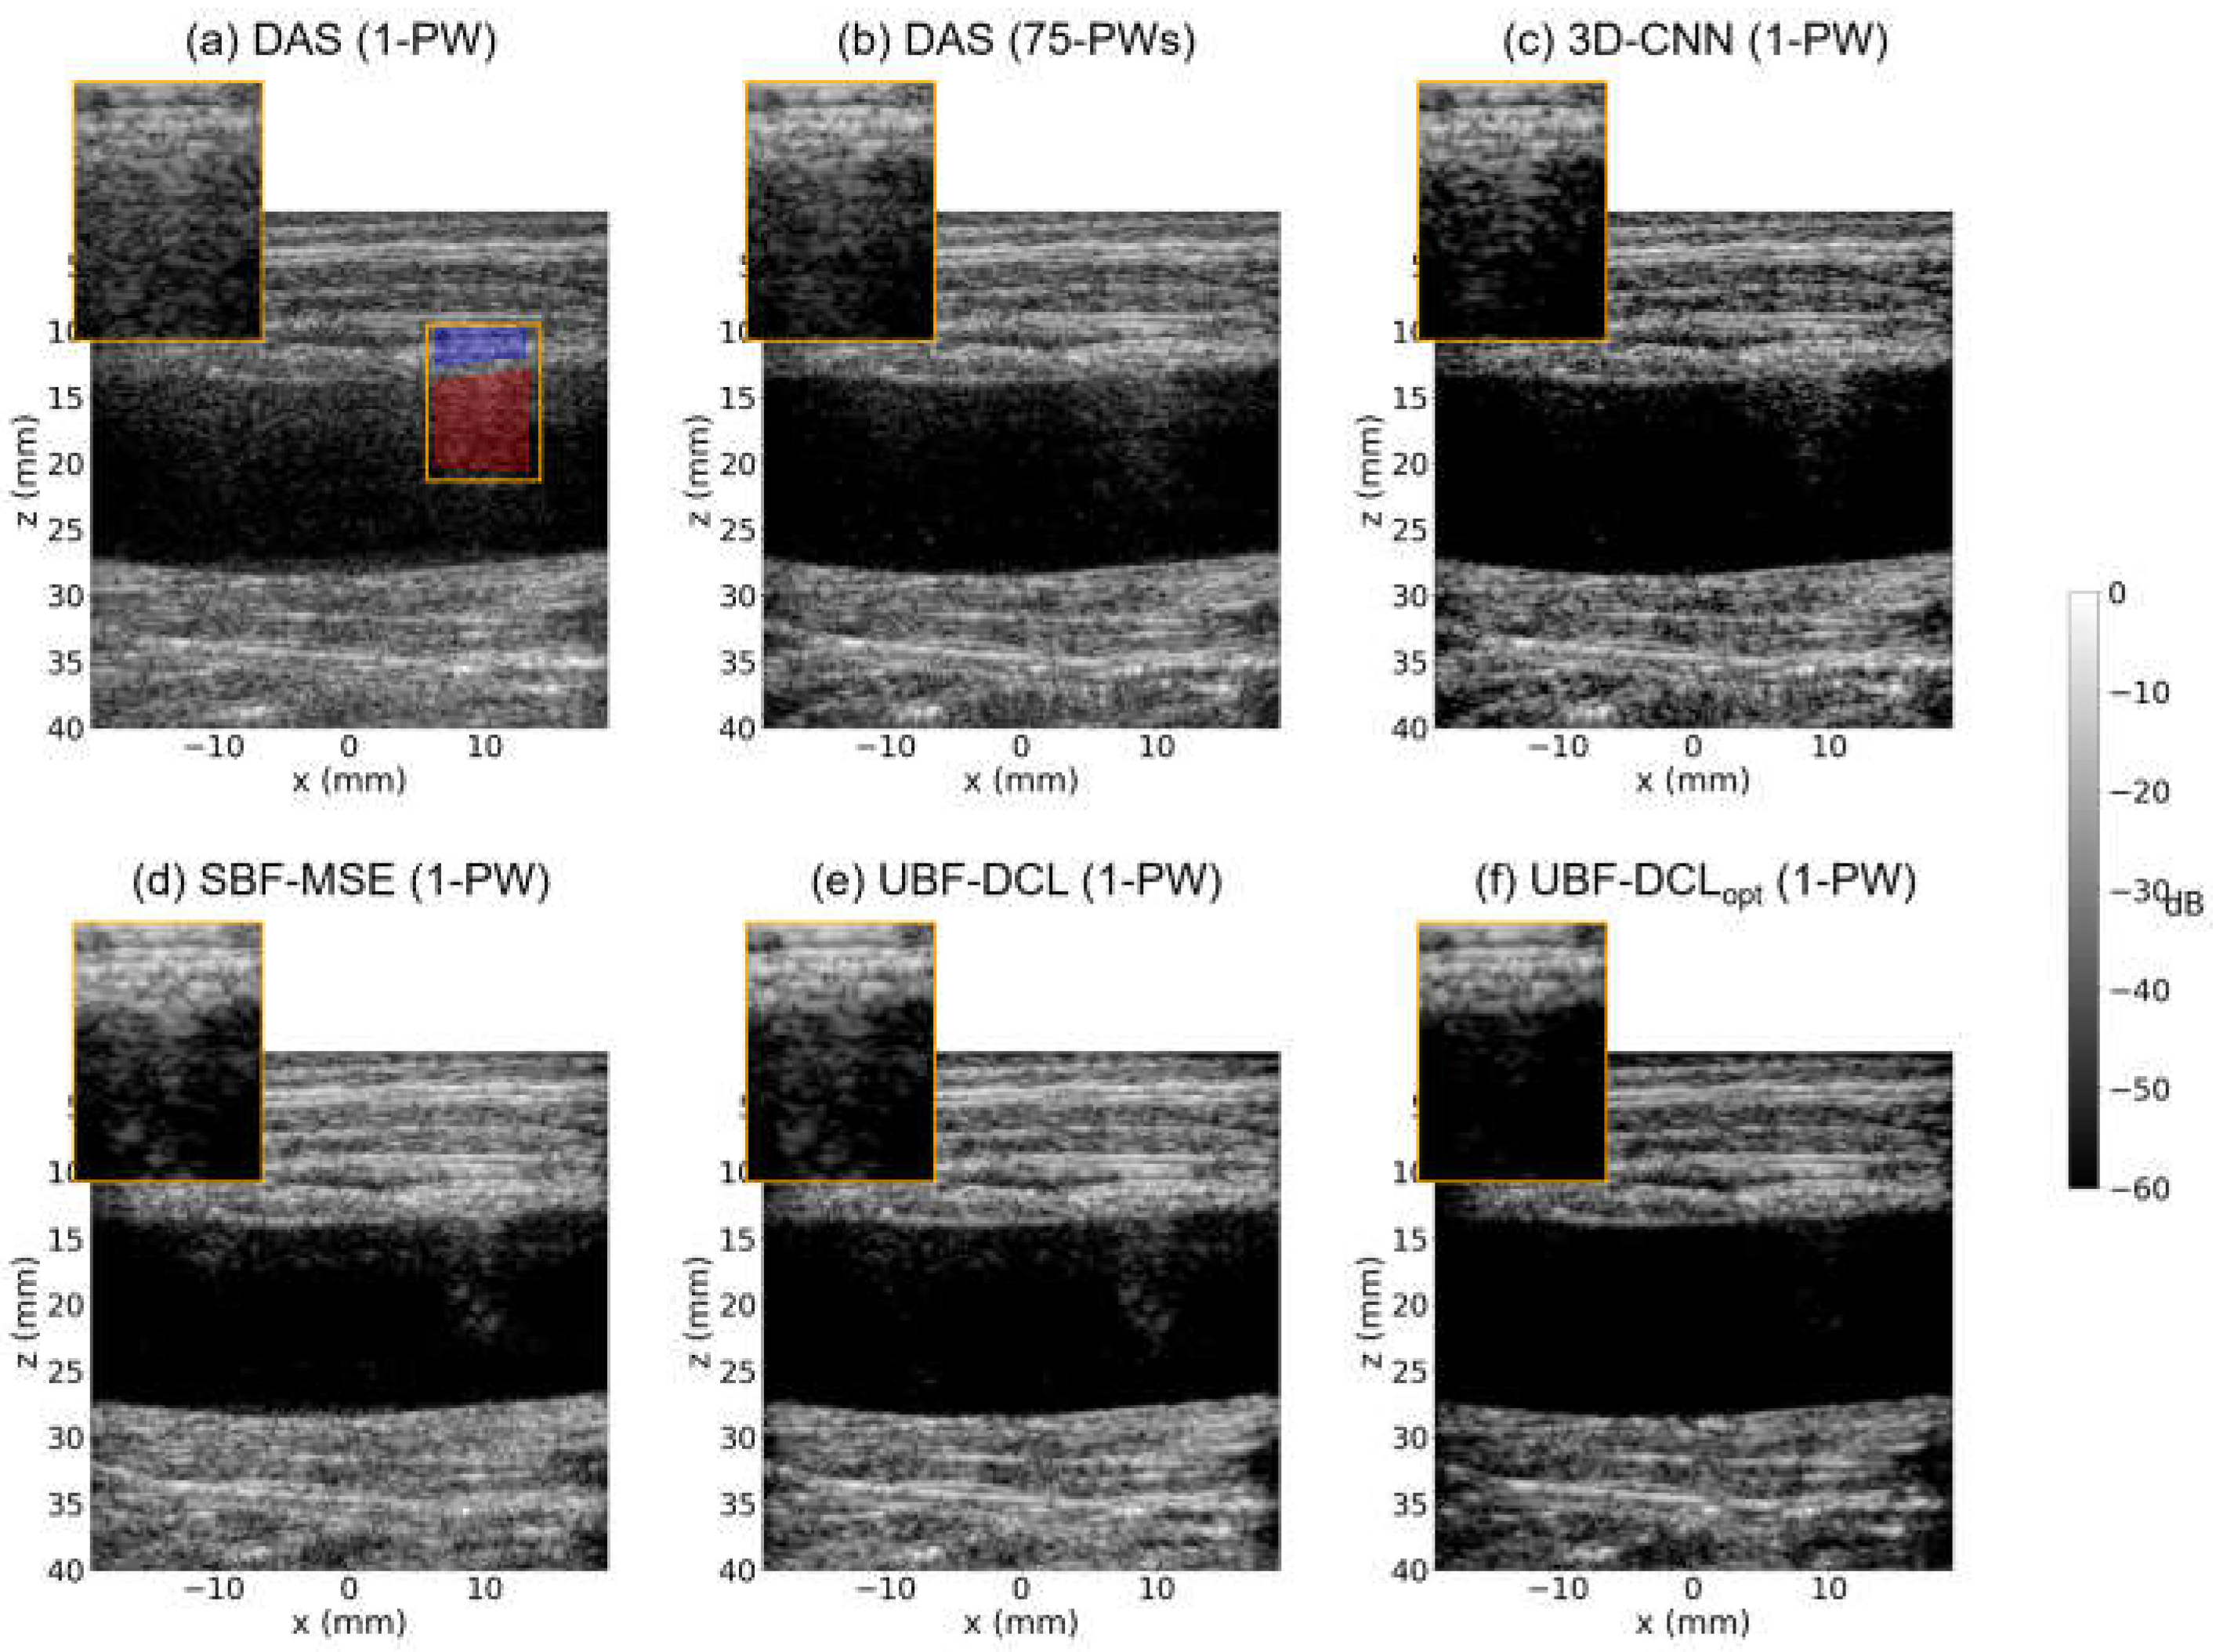

3.3. In Vivo Study—Carotid Artery

Among publicly available datasets, in vivo carotid artery with longitudinal view in PICMUS datasets was evaluated. Figure 7 shows B-mode imaging results for in vivo carotid artery using five different beamforming techniques, i.e., DAS (1 PW), DAS (75 PWs), 3-D CNN (1 PW), UBF-DCL (1 PW), and UBF-DCLopt (1 PW). As illustrated in Figure 7a, strong reverberation clutter artifacts are observed near the vessel wall, indicated by the orange ROI box, which is severely affected not only by reverberation but also by other clutter sources, such as sidelobe and grating lobe artifacts. The multi-PW reconstruction method (DAS with 75 PWs) still exhibits residual clutter artifacts, as shown in Figure 7b. In contrast, the three DL-based beamforming approaches, based on supervised or unsupervised learning (i.e., 3-D CNN, SBF-MSE, and UBF-DCL), substantially improve image quality by suppressing reverberation and other artifacts near the vessel region, as demonstrated in Figure 7c–e. The unsupervised beamforming method with optimized coherence loss (UBF-DCLopt) outperforms the other four comparison methods, enhancing the delineation of the vessel wall with clearly defined boundaries by effectively suppressing reverberation artifacts, as illustrated in Figure 7f. As also listed in Table 3, which presents the quantified results using the highlighted region in Figure 7a, the proposed UBF-DCLopt achieved the highest CNR and gCNR values, i.e., 5.65 dB and 0.97, representing a 32% improvement in CNR over the UBF-DCL method.

Figure 7. In vivo B-mode images of the carotid artery reconstructed using (a) DAS (1 PW), (b) DAS (75 PWs), (c) 3-D CNN (1 PW), (d) SBF-MSE, (e) UBF-DCL (1 PW), and (f) UBF-DCLopt (1 PW). The red and blue regions within the ROI were used for CNR and gCNR measurements.

Table 3. The measured CNR and gCNR values for all six comparison methods in the in vivo carotid artery.